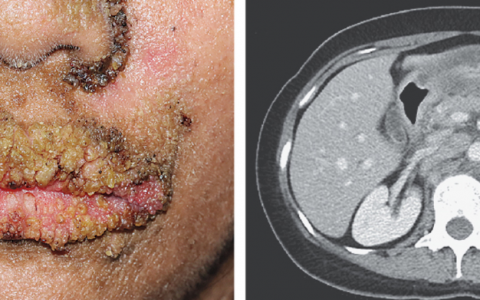

A 35-year-old man with a seven-day history of confusion(混乱), fever, chills(寒战), and cough is admitted to the hospital for evaluation. His blood pressure is 140/82 mm Hg, heart rate 108 beats/min, respiratory rate 28 breaths/min, temperature 37.9°C (100.2°F), and oxygen saturation 95% on room air. On clinical examination, he is in distress(痛苦) and can move the right upper and lower extremities but is hemiparetic(轻偏瘫) on the left. The right pupil(瞳孔) is dilated at 4 mm but reactive, and the left pupil is 2 mm and reactive. CT is shown below. He is intubated and started on IV ceftriaxone and vancomycin. His head is placed at 45 degrees, and a bolus of mannitol is administered.

这是一例继发于右侧基底神经节肿块的进行性神经功能恶化的年轻患者。他的临床表现表明即将发生疝。CT提示血管源性脑水肿,瞳孔不对称的临床检查提示腰椎穿刺可能风险太大,因为它将促进进一步向下的小脑幕切迹疝。类固醇的主要适应症是与脑肿瘤相关的血管源性水肿或伴随的脑照射和手术操作。尽管类固醇在这种模式中有益作用的确切机制尚不清楚,但类固醇降低了紧密连接通透性,进而稳定了被破坏的血脑屏障。有证据表明,治疗性低温可被认为是管理卒中和心脏骤停颅内高压的替代方法,但其用于感染性脑炎可能是有害的。可以考虑添加氨苄西林;但是,其不会对随后的小脑幕切迹疝产生任何影响。单核细胞增生李斯特菌虽然是普通人群中不常见的致病原因,但在孕妇、新生儿、老年人和免疫功能低下人群中是一种重要的病原体。